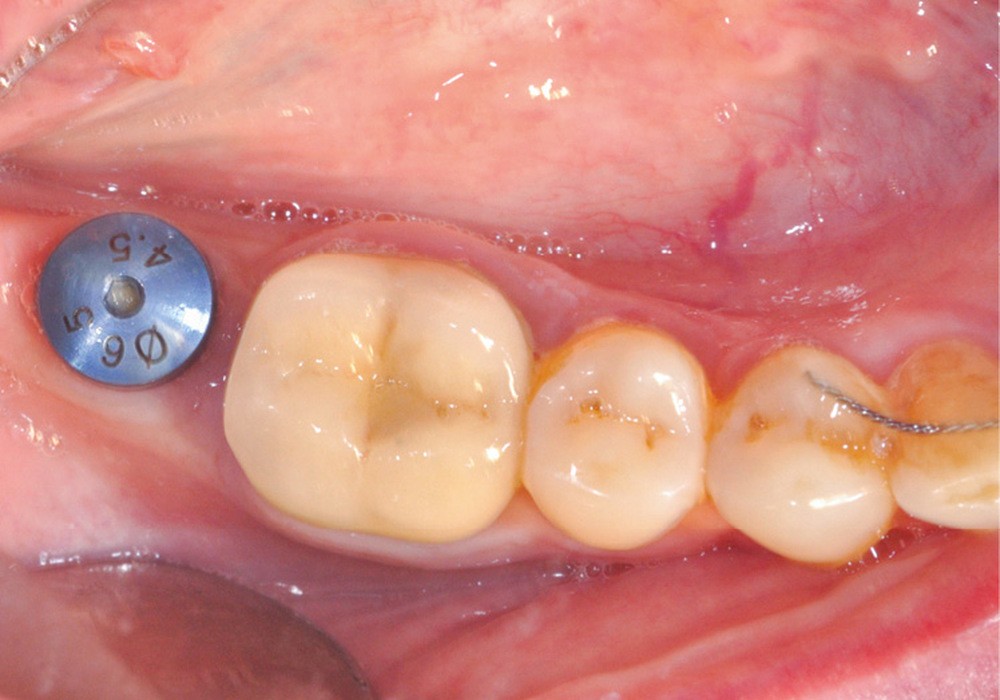

Une autre méthode, réalisable au cabinet, consiste à utiliser du silicone light en pistolet pour remplir l’intrados et, après la prise, désinsérer pour obtenir un duplicata rapide et économique (fig. 3).